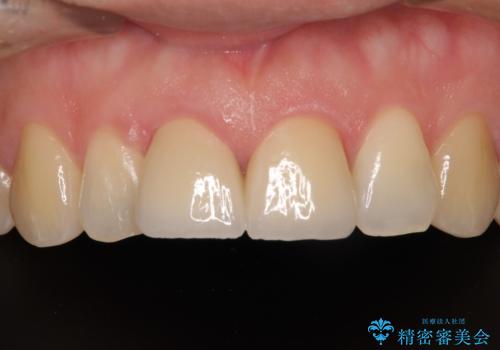

転んで欠けてしまった前歯 抜歯を回避してオールセラミッククラウンで審美回復

歯をぶつけてから1年後のレントゲン写真を取りましたが、どちらの歯も大きな異常は認められませんでした。

今後も定期的にレントゲン写真による経過観察が必要となります。